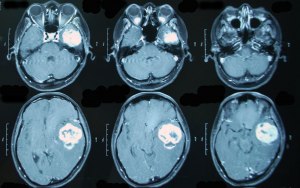

Может ли передаться генетически опухоль мозга?

1. Глиобластома мозга обычно не передается по наследству. Она чаще всего возникает из-за случайных изменений в генетической информации клеток мозга.

2. Однако, некоторые редкие наследственные синдромы могут увеличить риск развития опухоли мозга, включая генетические изменения, такие как нейрофиброматоз типа 1 и типа 2, ретинобластома, туберозный склероз и Li-Fraumeni синдром.

3. Если у отца была глиобластома мозга, его потомки могут иметь немного повышенный риск развития этого типа опухоли, чем общая популяция. Однако, это не означает, что они обязательно заболеют данной болезнью.

4. Следует также учитывать, что глиобластома мозга чаще возникает у взрослых людей, поэтому дети еще несовершеннолетних возрастов находятся в низком риске развития этой опухоли.

5. В целом, наследственный фактор играет меньшую роль в возникновении глиобластомы мозга, поэтому риск передачи болезни от родителя к ребенку остается невысоким.